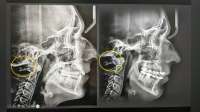

И челюгу отрастите

69 9080363

некоторым 13-14лвл на видео

азиата уже посадили?